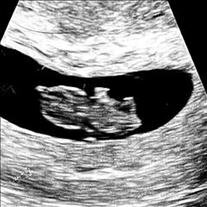

Luna Loera

October 12, 2023 - October 12, 2023

It is with heavy hearts that we share the passing of baby girl, Luna Loera, who, though eagerly anticipated by us, her loving parents, Gabriel and Katrina Loera, and three big brothers, Maverick, Jett, and Ryder Loera, was instead welcomed into... View Obituary & Service Information